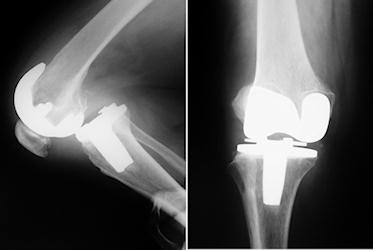

Total diz artroplastisi sonrasında tibio-femoral instabilite, iki ana başlık altında incelenebilir. Birinde artroplasti ile tekniği ile ilgili önemli bir sorun yoktur. Nadir bazı nöro-musküler hastalıkalar, polio (Giori NJ: J Bone Joint Surg 2002 84-A: 1157-61); multiple sclerosis (Rao V: J Bone Joint Surg 2003 85-A: 731-2) gibi kas gücünü ilgilendiren durumlarda instabilite ortaya çıkabilir. Buna karşın daha sık görülen oluş şekli, protezin teknik sorunları ile ilgilidir. Hareketli ara parçaların dislokasyonu (Ridgeway S: J Arthroplasty 2004, 19:686-93); Yumuşak dokuların zaman içinde esneyip uzaması; İlk ameliyatta kapsülo-ligamentöz dengenin sağlanamaması; Aşırı ya da yetersiz gevşetme ve Fleksiyon ve ekstansiyon aralığının eşit olmaması en sık görülen nedenlerdir. İnstabilite bazen bir travma sonrası ortaya çıkabilir. Bu sırada dizin stabilitesini sağlayan yapılarda ani ve şiddetli bir rüptür ortaya çıkar. Daha önceden zayıflamış veya gevşetilmiş olan bir bağın (ör. AÇB) atravmatik rüptürü de karşımıza çıkabilir. Son olarak, asimetrik polietilen aşınmasına bağlı göreceli laksite de oluşabilir (Resim 1 )(Krackow K: J Arthroplasty 2003, 18 (Suppl1): 45).İnstabilite tipleri

Sık görülen bir sorun varus-valgus düzleminde görülen instabilitedir. Sık olarak görülen varus dizlerde “Ne kadar laksite kabul edilebilir ?” sorusunun cevabı Ishii ve ark tarafından cevaplanmıştır. Varus-valgus yönünde 4mm’ye kadar olan açılmalarda sorun yaşanmadığı ancak daha fazla laksite olduğunda instabilite belirtilerinin ortaya çıktığı gösterilmiştir (Ishii Y:J Orthop Sci 2003; 8(4):538-42). Sanılanın aksine, gevşek olan dizlerde hareket açıklığı daha iyi değildir (Yamakado K: Arch Orthop Trauma Surg 2003, 123:1-4).Medio-lateral instabilite, primer artroplasti sonrası nadir olarak görülür. Aşırı gevşetme veya travma en önemli sebeptir. Valgus dizlerde lateral gevşetme sonrası derin fleksiyonda instabilite ortaya çıkabilir. Varus dizlerde, dizilim düzeltilmez ve ince insert kullanılırsa, medial taraftaki plastik aşınarak kırılacak ve instabilite oluşacaktır. Tedavi seçenekleri arasında, sadece insert değişimi, kollateral ligament rekonstrüksiyonu ve revizyon protezi sayılabilir.